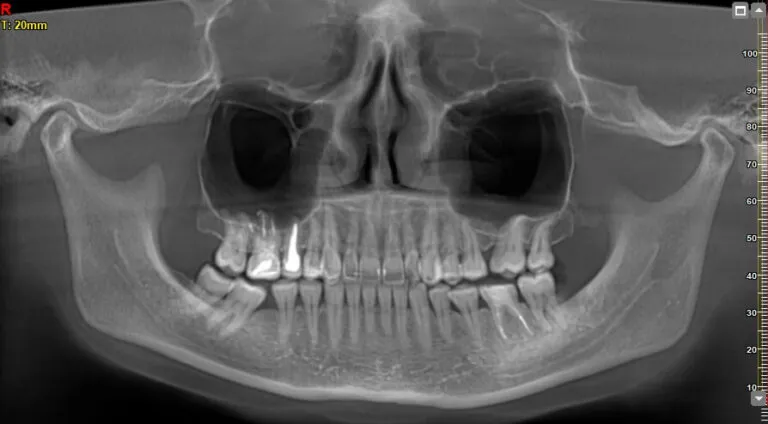

- Zdjęcie pantomograficzne (panoramiczne): ok. 100-150 zł

- Zdjęcie punktowe (okołowierzchołkowe): ok. 50 zł

- Tomografia komputerowa (CBCT): od 220 zł do 350 zł (niezbędna przy skomplikowanych ósemkach)

Diagnostyka to podstawa: ile zapłacisz za zdjęcie pantomograficzne lub tomografię?

Jak już wspomniałem, diagnostyka obrazowa jest często niezbędnym elementem przygotowania do ekstrakcji, zwłaszcza tej skomplikowanej. Zdjęcie pantomograficzne kosztuje zazwyczaj od 100 zł do 150 zł, punktowe około 50 zł, a tomografia komputerowa (CBCT), która daje trójwymiarowy obraz, to wydatek rzędu 220 zł - 350 zł. Te badania pozwalają chirurgowi dokładnie zaplanować zabieg i zminimalizować ryzyko.